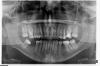

an_ver Опубликовано 2 мая, 2013 Поделиться Опубликовано 2 мая, 2013 Решил выровнять ось для дальнейшего протезирования Ссылка на комментарий

an_ver Опубликовано 2 мая, 2013 Автор Поделиться Опубликовано 2 мая, 2013 тогда я тем более не понимаю-за счёт каких сил зуб должен выправить свою ось в вашем кейсе,что за аппаратура и кто куда тянет?-на сколько вижу по снимку то место для постановки имплантата есть,и проблем с его установкой я не вижу, я вижу проблему в протетике,а именно не возможностью сделать коронку с опрой на имплантат с качественным контактным пунктом и с закрытием чёрного треугольника между коронкой на имплантате и 7толкать в моём предложении выше я подразумевал не корпусное перемещение,а именно выровнять ось,что как мне кажется если пациента заботит время,сэкономило бы его вполнеи если можно ещё вопрос по поводу по поводу корпусного перемещения 7 зуба вместо 6,есть ли у вас такие работы,очень интересно было бы посмотретьа с 7 зубом как минимум пломбу на контактной поверхности привести в порядок) ну это сейчас терапевты если заглянут скажут)спасибоПо поводу пломбы согласен с вами.Контактный пукт будет исправлен.По поводу аппаратуры...если вы заметили на 7 дуга загнута, дуга тут CuNiTi 018 и она активна,стремится линейно выпрямиться,7 будет вращаться вокруг оси против часовой стрелки.Работы есть.Фото нет,не было аппарата.Покопаюсь найду орто,выложу.А по поводу времени,снимок мой прицельный...по орто проблема еще с 16 (зубоальвеолярное удлинение) его еще подимать надо.Предпочитаю выравнивать оси зубов до протезирования и имплантации чтобы все было параллельно..Вы как поступаете?Орто выкладываю. Ссылка на комментарий

an_ver Опубликовано 2 мая, 2013 Автор Поделиться Опубликовано 2 мая, 2013 Вот и орто Ссылка на комментарий

an_ver Опубликовано 7 мая, 2013 Автор Поделиться Опубликовано 7 мая, 2013 тогда я тем более не понимаю-за счёт каких сил зуб должен выправить свою ось в вашем кейсе,что за аппаратура и кто куда тянет?-на сколько вижу по снимку то место для постановки имплантата есть,и проблем с его установкой я не вижу, я вижу проблему в протетике,а именно не возможностью сделать коронку с опрой на имплантат с качественным контактным пунктом и с закрытием чёрного треугольника между коронкой на имплантате и 7толкать в моём предложении выше я подразумевал не корпусное перемещение,а именно выровнять ось,что как мне кажется если пациента заботит время,сэкономило бы его вполнеи если можно ещё вопрос по поводу по поводу корпусного перемещения 7 зуба вместо 6,есть ли у вас такие работы,очень интересно было бы посмотретьа с 7 зубом как минимум пломбу на контактной поверхности привести в порядок) ну это сейчас терапевты если заглянут скажут)спасибоВот орто,которые обещал Ссылка на комментарий